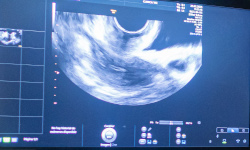

En l’àmbit diagnòstic, la unitat realitza anualment entre 150 i 200 ecografies de sòl pelvià (des del 2021) i 200-250 urodinàmies (des del maig del 2025) al nostre centre. Pel que fa al tractament, es duen a terme unes 130 pacients intervingudes d'incontinència urinària o prolapse anualment, a més de 150-200 tractaments de rehabilitació de sòl pelvià, amb una tendència creixent degut a l’augment de la demanda.

La unitat ofereix un ampli ventall de proves diagnòstiques, com ecografia de sòl pelvià, ecografia endoanal, urodinàmia i manometria, i diferents opcions terapèutiques.

- Proves diagnòstiques: ecografia de sòl pelvià i endoanal, urodinàmia i manometria, les dues últimes integrades enguany al nostre centre.